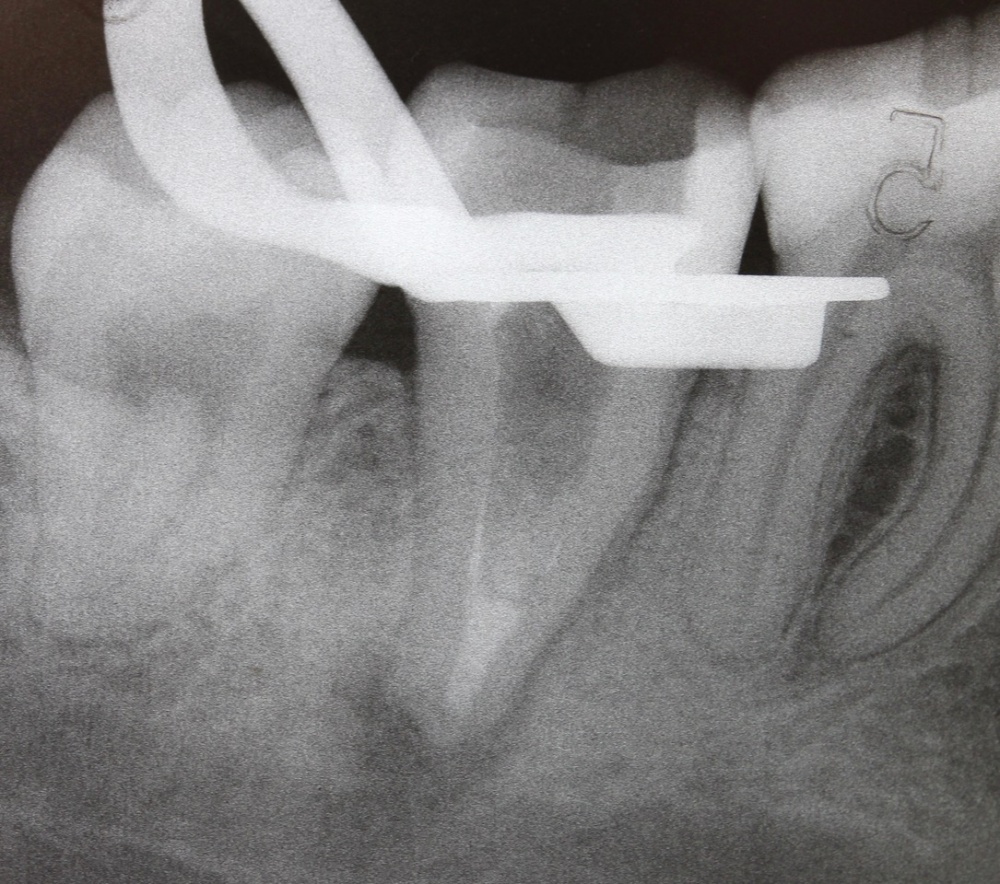

Im nächsten Fall stellte sich ein Patient mit reizunabhängigen Beschwerden und Perkussionsempflindlichkeit an Zahn 17 vor. Begleitend lag eine Lockerung Grad I bis II vor. Das daraufhin angefertigte Röntgenbild (Abb. 5) zeigt eine insuffiziente Wurzelfüllung, nebst Wurzelstift und einer umfangreichen apikalen Osteolyse. Darüber hinaus scheint Zahn 16 ebenfalls apikal beherdet zu sein und im Bereich der mesialen Wurzel besteht der Verdacht eines frakturierten Wurzelkanalinstrumentes.

Nach ausführlicher Aufklärung der vorhandenen Therapiealternativen entschied sich der Patient für die Revisionsbehandlung. Diagnostisch wichtig war in diesem Fall die Bestimmung des inserierten Wurzelstiftes. Röntgenologisch unterscheiden sich Glasfaser- und Metallstifte aufgrund der physikalischen Eigenschaften des Materials deutlich, sodass es sich hier zweifelsfrei um einen Metallstift handelte. Durch das röntgenologisch sichtbare Gewinde ließ sich die Art des Stiftes bestimmen. So war nach Entfernen der Krone das vorsichtige Freischleifen des Stiftkopfes (Abb. 6) wichtig, um den Stift mit einem speziellen Schlüssel ausdrehen zu können (Abb. 7).